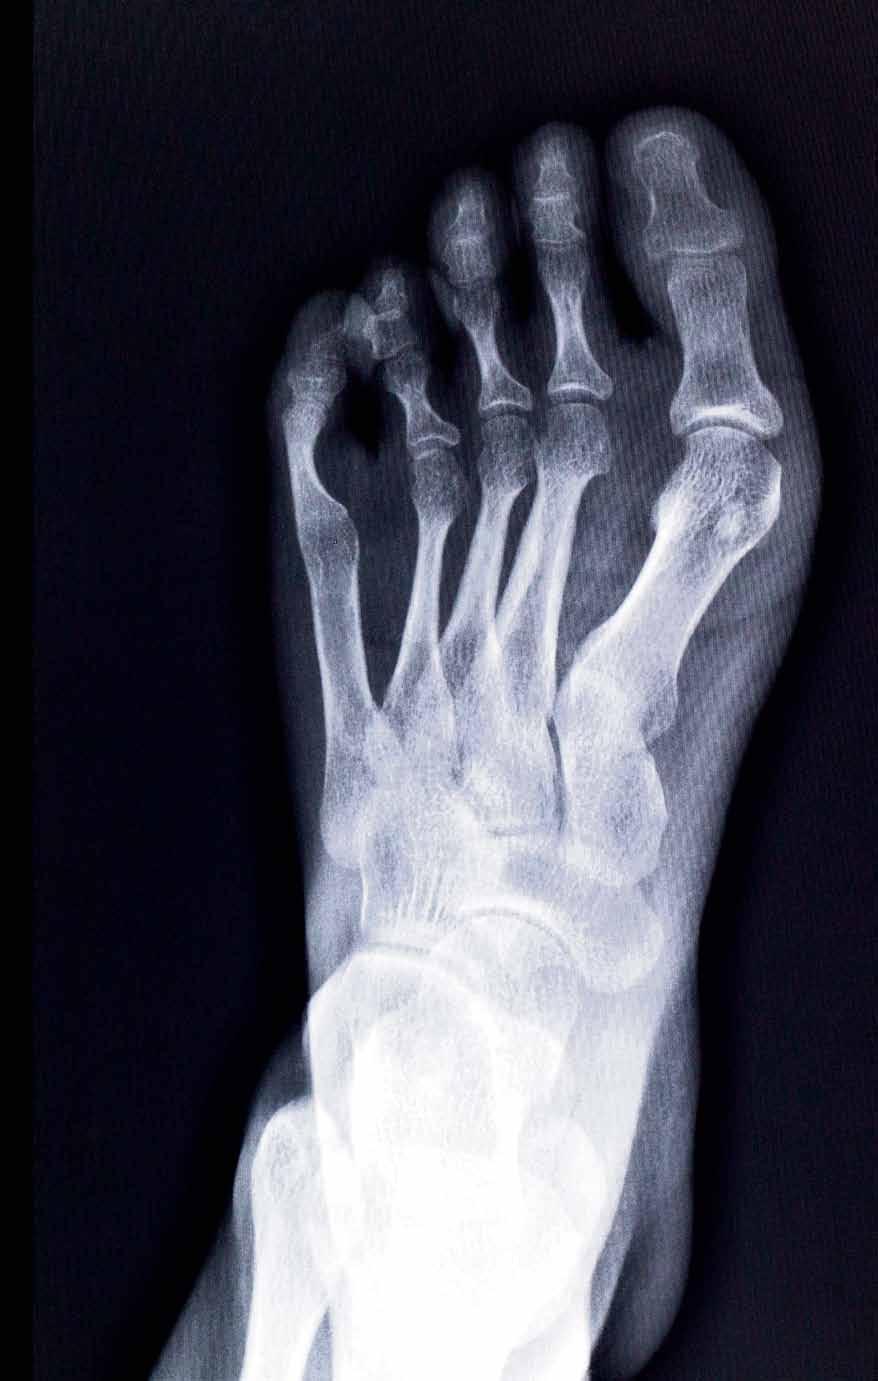

18 "Κότσι": Τελικά το χειρουργείο είναι η μοναδική κατάληξη;